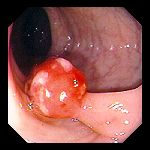

Ce que l'on observe lors d'une coloscopie

![]() |

Polype pédiculé

|

Polype sessile